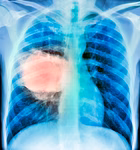

Rak pluća se dugo smatrao bolešću pušača, no kako je upotreba duhana opala u mnogim dijelovima svijeta, pojavio se zabrinjavajući problem: rak pluća kod osoba koje nikada nisu pušile je u porastu. Ova vrsta raka pogađa žene, osobito one azijskog podrijetla, i češće se pojavljuje u istočnoazijskim nego u zapadnim zemljama, prenosi Klix.ba.

Tim je analizirao rak pluća kod 871 osobe koja nikada nije pušila, a žive u 28 regija s različitim razinama zagađenja zraka diljem Afrike, Azije, Europe i Sjeverne Amerike. Koristeći sekvenciranje cijelog genoma, istraživači su identificirali različite obrasce DNK mutacija, poznate kao mutacijski potpisi.

Kombinirajući ove genomske podatke s procjenama zagađenja, istraživači su uspjeli procijeniti dugoročnu izloženost pojedinaca zagađenju zraka. Otkrili su da osobe koje nikada nisu pušile, a žive u zagađenijem okruženju, imaju znatno više mutacija u tumorskom tkivu pluća – osobito mutacija pokretača, koje izravno potiču razvoj raka i specifičnih mutacijskih potpisa.

Osim zagađenja zraka, identificiran je još jedan rizik: aristolohinska kiselina – kancerogen koji se nalazi u nekim tradicionalnim kineskim biljnim pripravcima. Specifičan mutacijski potpis povezan s aristolohinskom kiselinom pronađen je gotovo isključivo u slučajevima raka pluća kod osoba s Tajvana koje nikada nisu pušile.